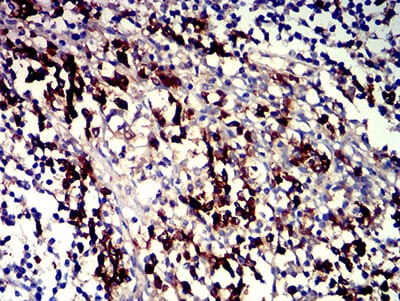

- Immunohistochemical analysis of paraffin-embedded human tonsil tissues using CD319 mouse mAb with DAB staining.

- Immunohistochemical analysis of paraffin-embedded human rectum cancer tissues using CD319 mouse mAb with DAB staining.